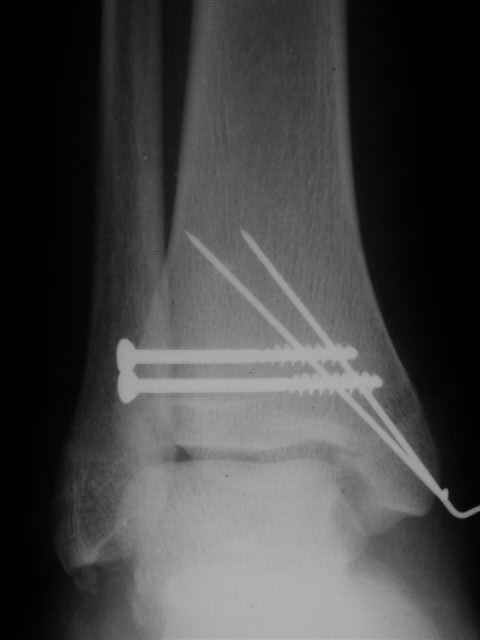

В первом письме я упомянул о закрытом повреждении правого голеностопного сустава, эверсионно-пронационный механизм травмы - перелом внутренней лодыжки( поперечный, на уровне суставной щели) и отрывной перелом бугорка Chaput. После обработки открытых переломов бедра и большеберцовой кости в эту же сессию перелом внутренней лодыжки фиксировал двумя расходящимися спицами, бугорок Chaput двумя тягловыми винтами 3,5 мм. Раны заживают благополучно. Учитывая повреждение наружной группы мышц, активное разгибание в голеностопном суставе ограничено. Пассивная + пассивно-активная мобилизация голеностопного сустава с физиотерапевтом.

Я предупреждал, что ничего сверхъестественного. Каюсь, что одна из спиц прошла несколько дальше, чем нужно было, но главное - перелом стабилизирован и больной работает суставом в полном объёме, несмотря на представленную раннее травму коленного сустава.

Всего вам Доброго,

Евгений И Чекашкин